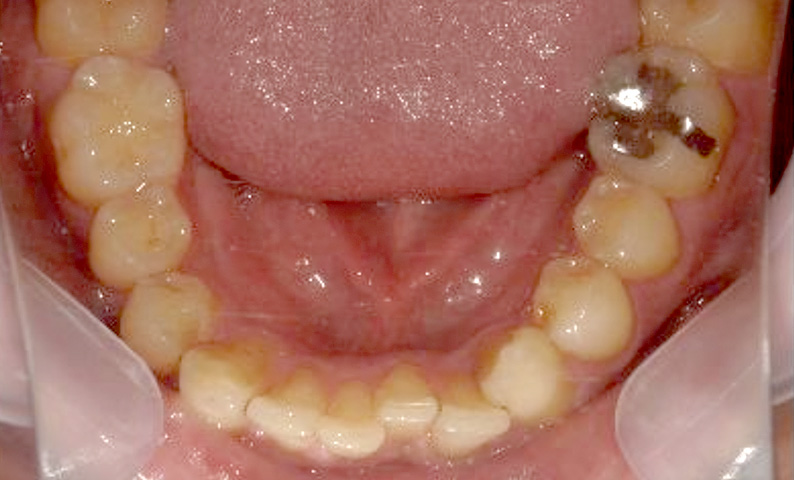

症例_003 下顎だけの部分矯正

治療期間:10ヶ月金額:24万円+税女性前歯のガタガタ下の前歯だけ上顎は補綴治療中

| Before | After |